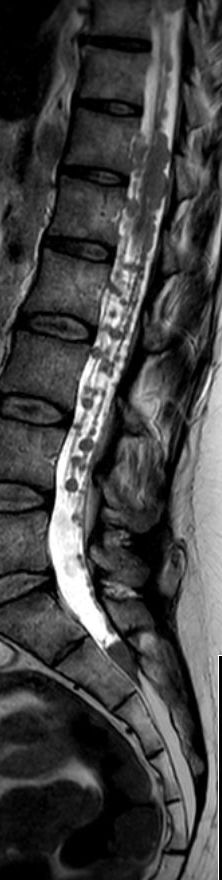

Rückenmarks-Metastasen

48-jährige Patientin mit einem kleinzelligen, neuroendokrinen Bronchialkarzinom. Taubheit der Füße, Kraftminderung und Hypästhesie beider Beine.

RM-Metastasen

Rückenmarks-Metastasen Rückenmarks-Metastasen Rückenmarks-Metastasen